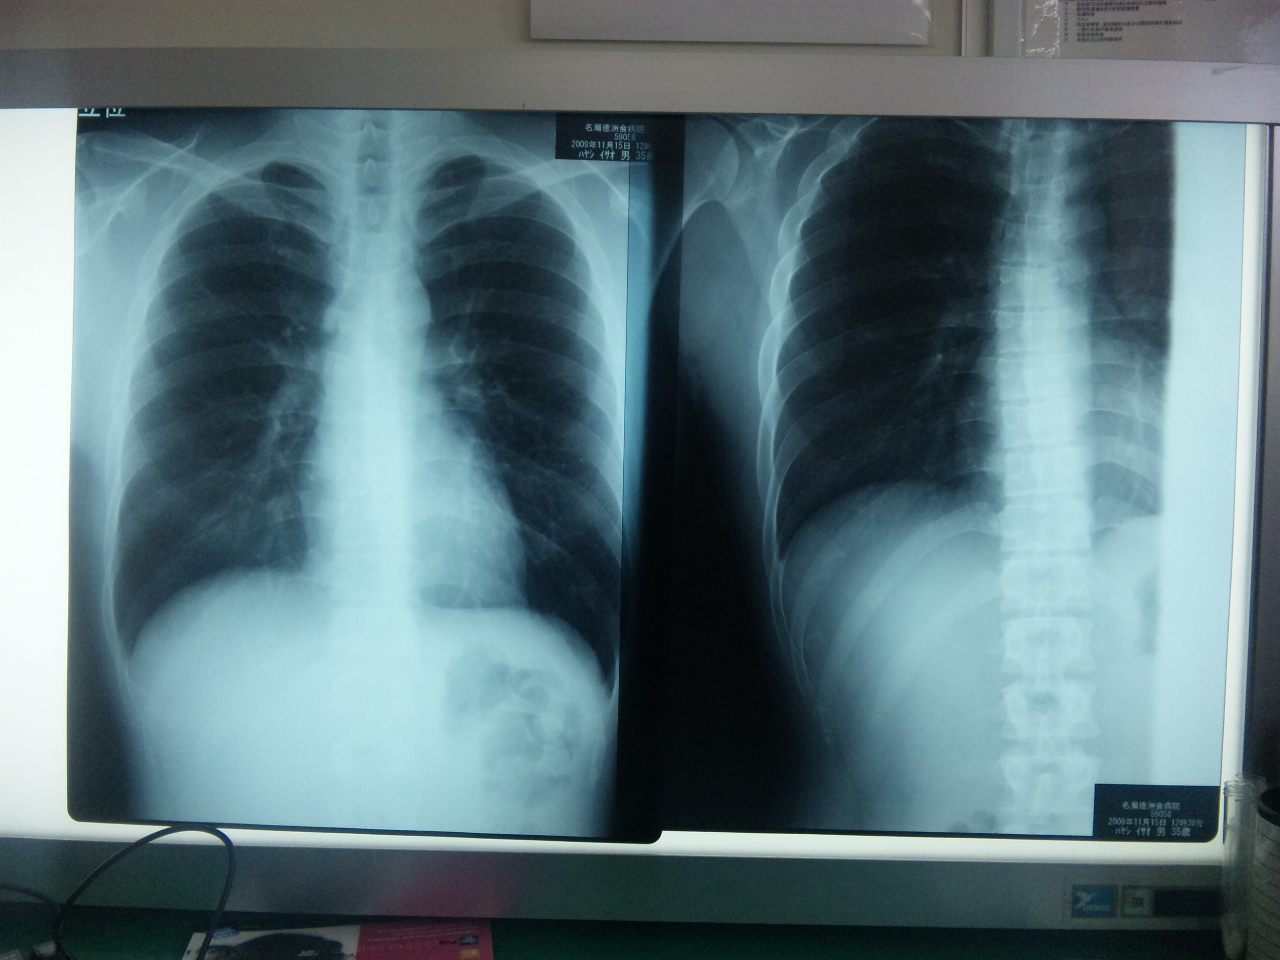

日に日に痛みが増すから四日目に骨折を疑って病院に行ってきた。

レントゲンでは小さなひびは写らないらしく、しばらくしても痛かったらまた来てくれと鎮静剤とシップをもらってきた。保険証あってマジに助かった。アートクラスさせてくれてるPicoに感謝